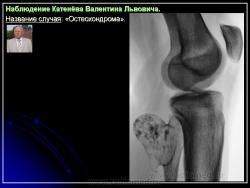

Наблюдение Катенёва В.Л.

Приложения:

1.201607190013.jpg2.201607190017.jpg3.201607190018.jpg4.201607190016.jpg5.201607190019.jpg6.201607190020.jpg7.201607190021.jpg